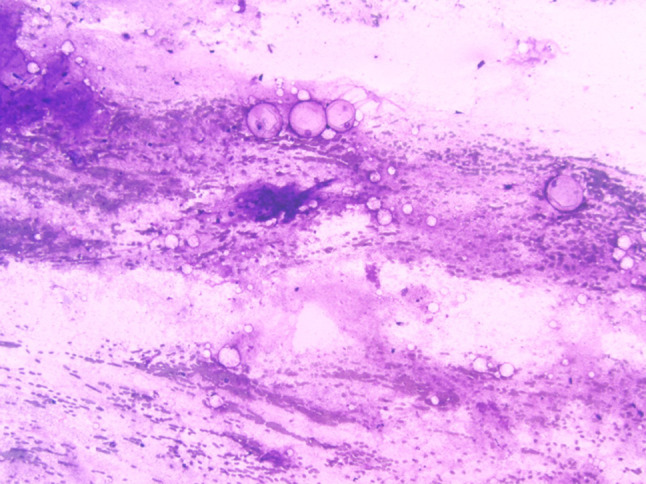

Fig. 3.

Low-grade mucoepidermoid carcinoma cyst lining showing admixed mucinous and squamous epithelial cells (Mucicarmine stain, magnification × 20)